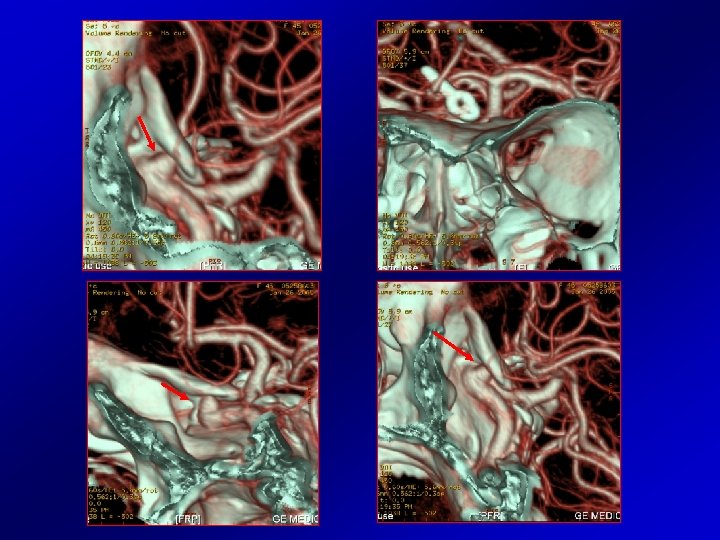

Pt 10 male 25 y. o. Pre-treatment DSA 07 -1998 Post-treatment angiograms 03 -1999: note the regular profile of the cavernous and ophthalmic R ICA and absence of lesions in the L MCA trifurcation

First follow up CTA (05 -2005) demonstrated a de novo lesion located on the ophthalmic R ICA (white arrows).

Last CTA (02 -2009) shows slight progressive increase of the aneurysm located on R ICA, also depicting another, smaller lesion on the trifurcation of L MCA (green arrows).

The retrospective review of first CTA (05 -2005) demonstrated the presence of the second de novo aneurysm, on the L MCA.